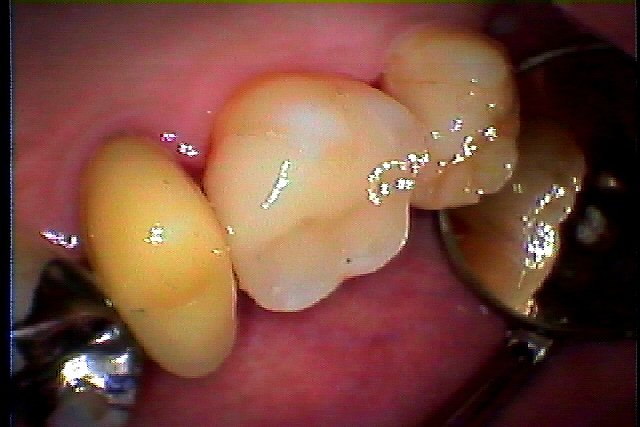

セラミック治療へ。 こんな感じで虫歯の治療より審美治療へ変わります。| |広島市安佐南区の歯科医院 セラミック治療へ。 こんな感じで虫歯の治療より審美治療へ変わります。 トップ お知らせ・ブログ セラミック治療へ。 こんな感じで虫歯の治療より審美治療へ変わります。 セラミック治療へ。 こんな感じで虫歯の治療より審美治療へ変わります。 Web診療予約 初めての方へ 選ばれ続ける理由 院内設備について 歯が痛いしみる一般歯科 歯がぐらぐらする歯周病 健康な歯を保ちたい予防歯科 子供の虫歯予防をしたい小児歯科 銀歯をセラミックに審美歯科 白い歯を目指しませんか?ホワイトニング 矯正専門医がいるので安心矯正歯科 抜けた歯を補いたいインプラント・入れ歯 医院案内 スタッフ紹介 メリィハウス歯科クリニックオフィシャルホームページ ラベンダー歯科クリニックオフィシャルホームページ お知らせ・ブログ ホーム 診療科目 一般歯科 歯周病治療 予防治療 小児歯科 審美治療 ホワイトニング 矯正歯科 入れ歯・インプラント マウスピース矯正 初めての方へ 院長・スタッフ 設備紹介 医院案内・アクセス メニューを閉じる